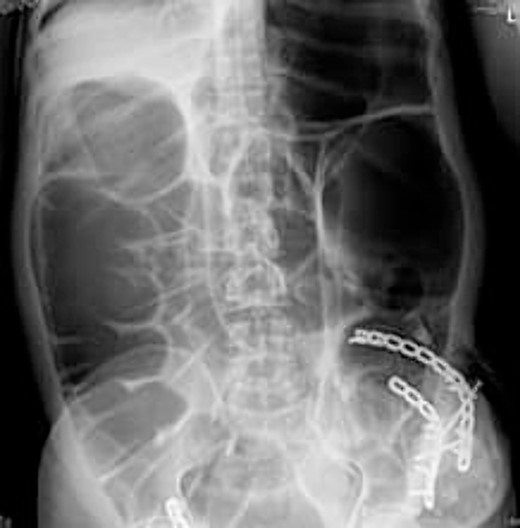

Radio imaging was requested for the patient at admission. Erect X.R. has been taken, showing dilated bowel loops (Figs 3 and 4).